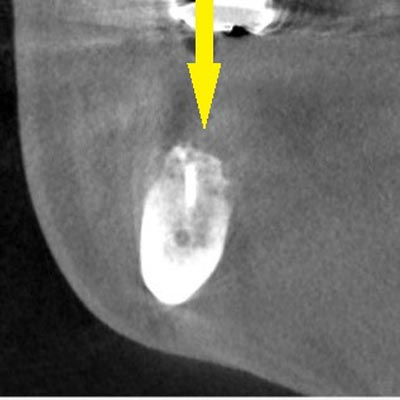

手術後の、別な方向からみたCT画像です。術前に大きく吸収されていた部分に、骨のブロックが移植され、骨が造成されています。真っ白にピンのように写るのは、骨を固定した小さなスクリューです。

手術後の、別な方向からみたCT画像です。術前に大きく吸収されていた部分に、骨のブロックが移植され、骨が造成されています。真っ白にピンのように写るのは、骨を固定した小さなスクリューです。